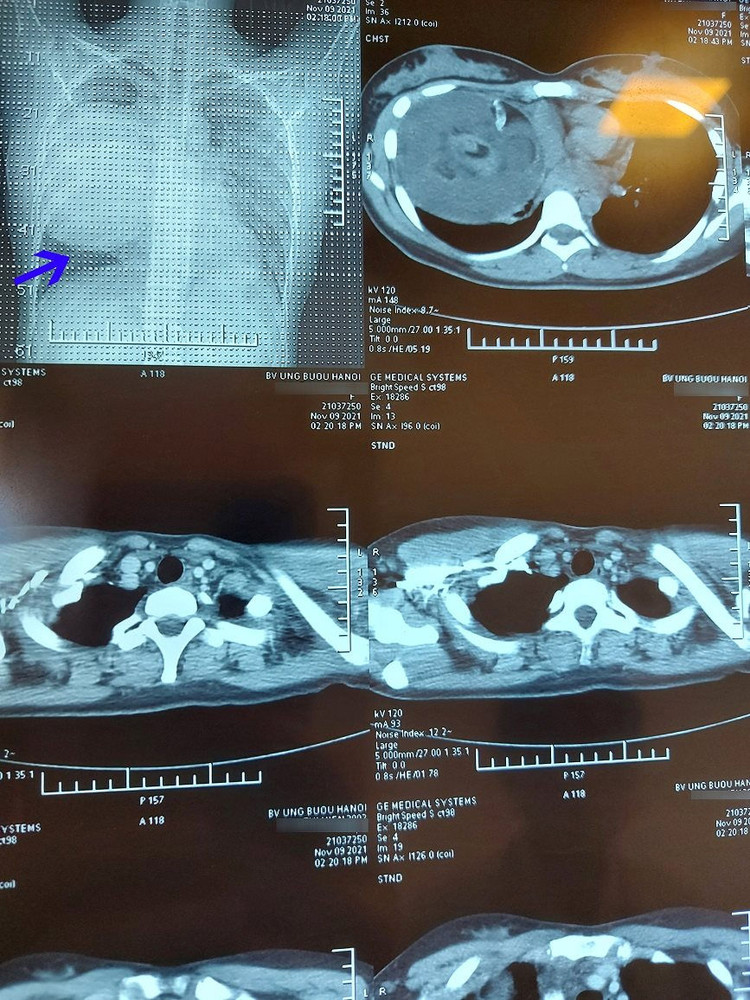

Các bác sĩ bệnh viện Ung bướu Hà Nội vừa phẫu thuật lấy khối u quái khổng lồ trong lồng ngực cô gái 19 tuổi. Khối u to, đè đẩy tim, chèn ép làm xẹp phổi, dính nhiều cơ quan nội tạng xung quanh.

Bệnh nhân nữ 19 tuổi ở Phú Xuyên, Hà Nội được phát hiện có u quái nằm trong lồng ngực gây tức ngực, khó thở. Đặc biệt, kích thước u rất lớn với đường kính khoảng 20cm nên phẫu thuật tương đối phức tạp.

TS.BS. Phan Lê Thắng, Trưởng khoa Ngoại Theo yêu cầu, Bệnh viện Ung bướu Hà Nội cho biết, vị trí u nằm ở trung thất trước trên bên phải, tổ chức u có cả lông, tóc, mỡ, xương. Khối u to, đè đẩy tim, chèn ép làm xẹp phổi, dính nhiều cơ quan nội tạng xung quanh. Loại u quái nằm trong trung thất rất hiếm gặp.

Phẫu thuật thành công đã giúp giải phóng khối u khỏi cơ thể, nở phổi giúp tăng diện tích thở cho bệnh nhân, quan trọng hơn là tránh được những biến chứng nặng sau này về tuần hoàn và tim mạch nếu để u tiếp tục phát triển.